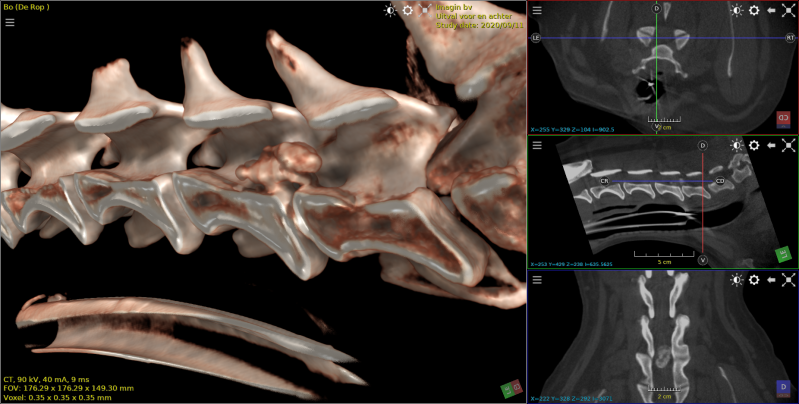

cocker met hernia  c2-c3